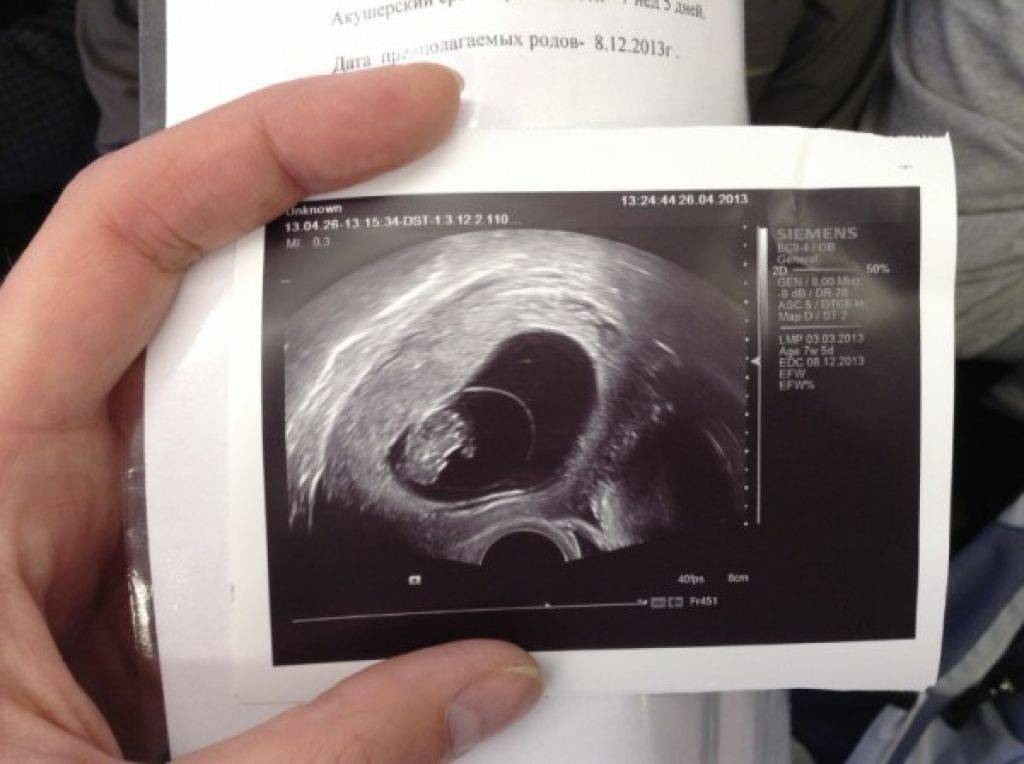

Развитие эмбриона: Что происходит на 3 неделе беременности

Раздел: Фотопанорама